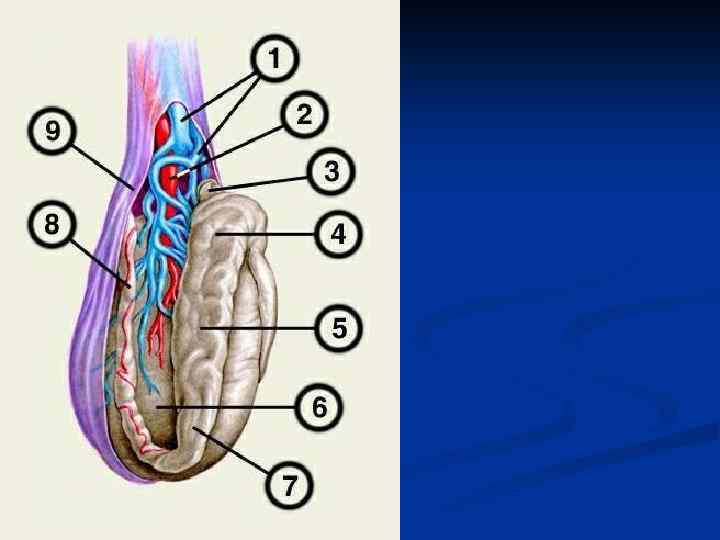

Семенной канатик, funiculus spermaticus – круглый тяж (15 -20 см) от глубокого пахового кольца до верхнего конца яичка, образующийся в процессе опускания яичка. Состав: 1. Семявыносящий проток 2. Яичковая артерия 3. Артерия семявыносящего протока 4. Лозовидное венозное сплетение 5. Лимфатические сосуды яичка и придатка 6. Нервы 7. Влагалищный отросток Оболочки, tunicae funiculi spermatici (изнутри наружу): 1. Внутренняя семенная фасция 2. Мышца поднимающая яичко 3. Фасция мышцы поднимающей яичко 4. Наружная семенная фасция

Семенной канатик, funiculus spermaticus – круглый тяж (15 -20 см) от глубокого пахового кольца до верхнего конца яичка, образующийся в процессе опускания яичка. Состав: 1. Семявыносящий проток 2. Яичковая артерия 3. Артерия семявыносящего протока 4. Лозовидное венозное сплетение 5. Лимфатические сосуды яичка и придатка 6. Нервы 7. Влагалищный отросток Оболочки, tunicae funiculi spermatici (изнутри наружу): 1. Внутренняя семенная фасция 2. Мышца поднимающая яичко 3. Фасция мышцы поднимающей яичко 4. Наружная семенная фасция